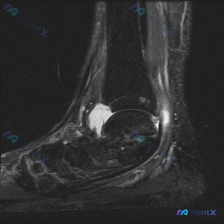

病例影像读片分享 今天整理了一例踝关节MRI的读片资料,把分析思路分享给大家一起讨论。 基本影像信息 这是一张踝关节矢状位T2加权MRI,可以清晰显示胫骨远端、距骨、跟骨、舟骨、楔骨等踝关节复合体骨性结构,T2序列对液体信号显示清晰。 核心阳性发现 1. 多关节广泛积液:胫距关节前后隐窝、距下关节间...

最近看到一份踝关节MRI读片请求,问题是「影像中能观察到什么?提示软组织积液」,整理了完整的读片和分析思路,和大家分享讨论。 一、影像基本信息 这是踝关节矢状位MRI T2序列,影像观察结果如下: 1. 骨结构:胫骨远端、距骨、跟骨、舟骨、部分楔骨骨皮质轮廓完整,胫距关节间隙可见 2. 关节腔:胫距...

看到这个踝关节MRI的读片请求,问题是观察到的软组织积液,我整理了完整的影像和分析思路分享给大家。 病例影像基础信息 这是踝关节MRI矢状位T2序列图像,核心观察结果如下: 1. 骨骼系统:胫骨远端、距骨、跟骨、舟骨骨皮质完整,未见明确骨折线;距骨体及跟骨骨髓信号均匀,无明显水肿或硬化改变 2. 关...

今天给大家分享一张踝关节MRI矢状位T2加权影像的读片分析,病例本身并不复杂,但这种仅表现为少量积液的情况,临床其实很容易走偏,整理一下完整的思考过程给大家参考。 一、影像核心信息整理 这张是踝关节矢状位T2加权MRI,我们先把所有明确的影像信息理清楚: 1. 骨骼结构:胫骨远端、距骨、跟骨、舟骨骨...

看到一份很有代表性的踝关节MRI影像,整理了资料和分析思路分享给大家。 病例影像基本信息 这是一份踝关节矢状位T2加权像(T2WI),先给大家说下客观观察到的结果: 1. 解剖结构显示清晰:可以看到胫骨远端、距骨、跟骨、足舟骨及部分跖骨 2. 核心异常发现: - 胫距关节腔前方、后方可见明显T2高信...